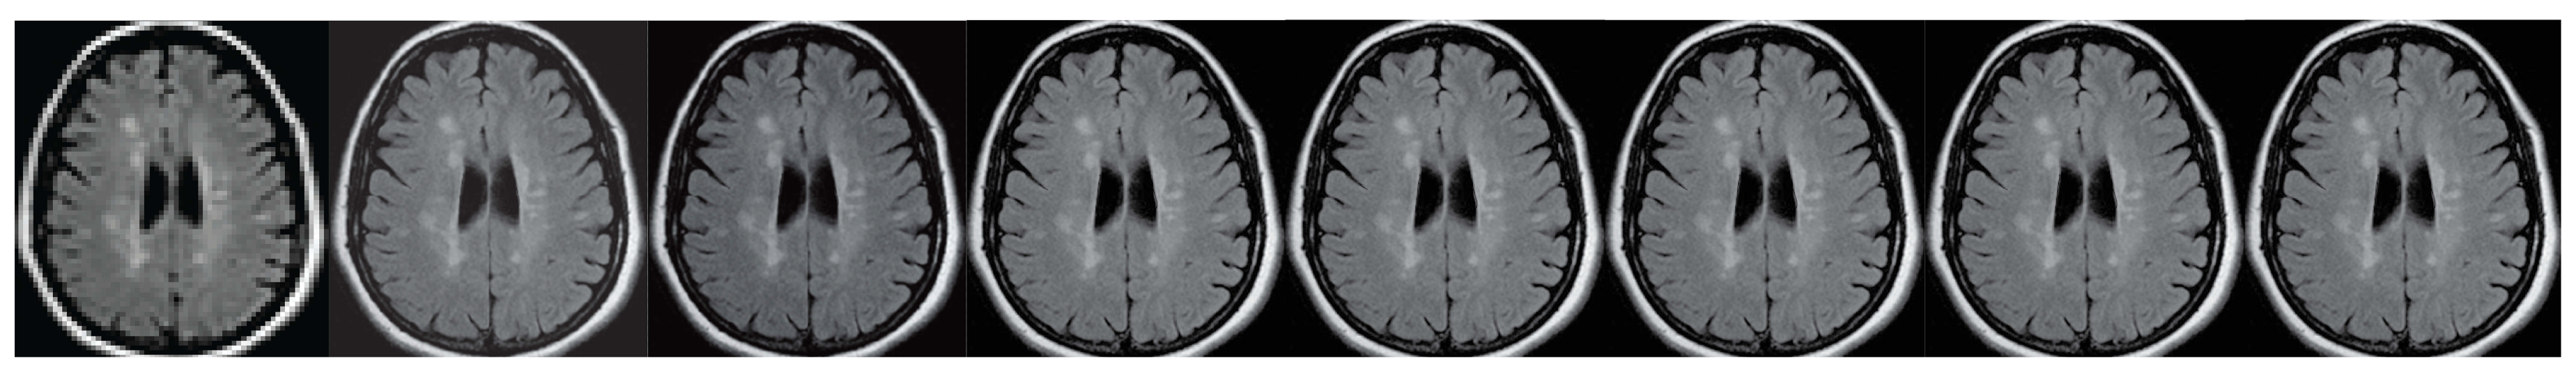

Figure 6. A brain imaging example. From left to right: A: Image reconstructed from partially sampled PROPELLER blade, B:Cartesian sampling grid without image registration applied (with no downsampling applied), C: B-spline Cubic interpolation, D: Non-Rigid Multi-Modal 3D Medical Image Registration Based on Foveated Modality Independent Neighbourhood Descriptor [45], E: Enhanced deep residual networks for single image super-resolution [14], F: Image super-resolution using very deep residual channel attention networks [16], G: Residual dense network for image super-resolution [15], H: super-resolution with proposed sampling scheme and motion compensation (the proposed algorithm). Compression ratio is 50%. Please see Table 1 for the PSNR values at other compression ratios.

Figure 7. The brain imaging results. From left to right: A: Image reconstructed from partially sampled PROPELLER blade, B:Cartesian sampling grid without image registration applied (with no downsampling applied), C: B-spline Cubic interpolation, D: Non-Rigid Multi-Modal 3D Medical Image Registration Based on Foveated Modality Independent Neighbourhood Descriptor [45], E: Enhanced deep residual networks for single image super-resolution [14], F: Image super-resolution using very deep residual channel attention networks [16], G: Residual dense network for image super-resolution [15], H: super-resolution with proposed sampling scheme and motion compensation (the proposed algorithm). Compression ratio is 50%. Please see Table 2 for the PSNR values at other compression ratios.